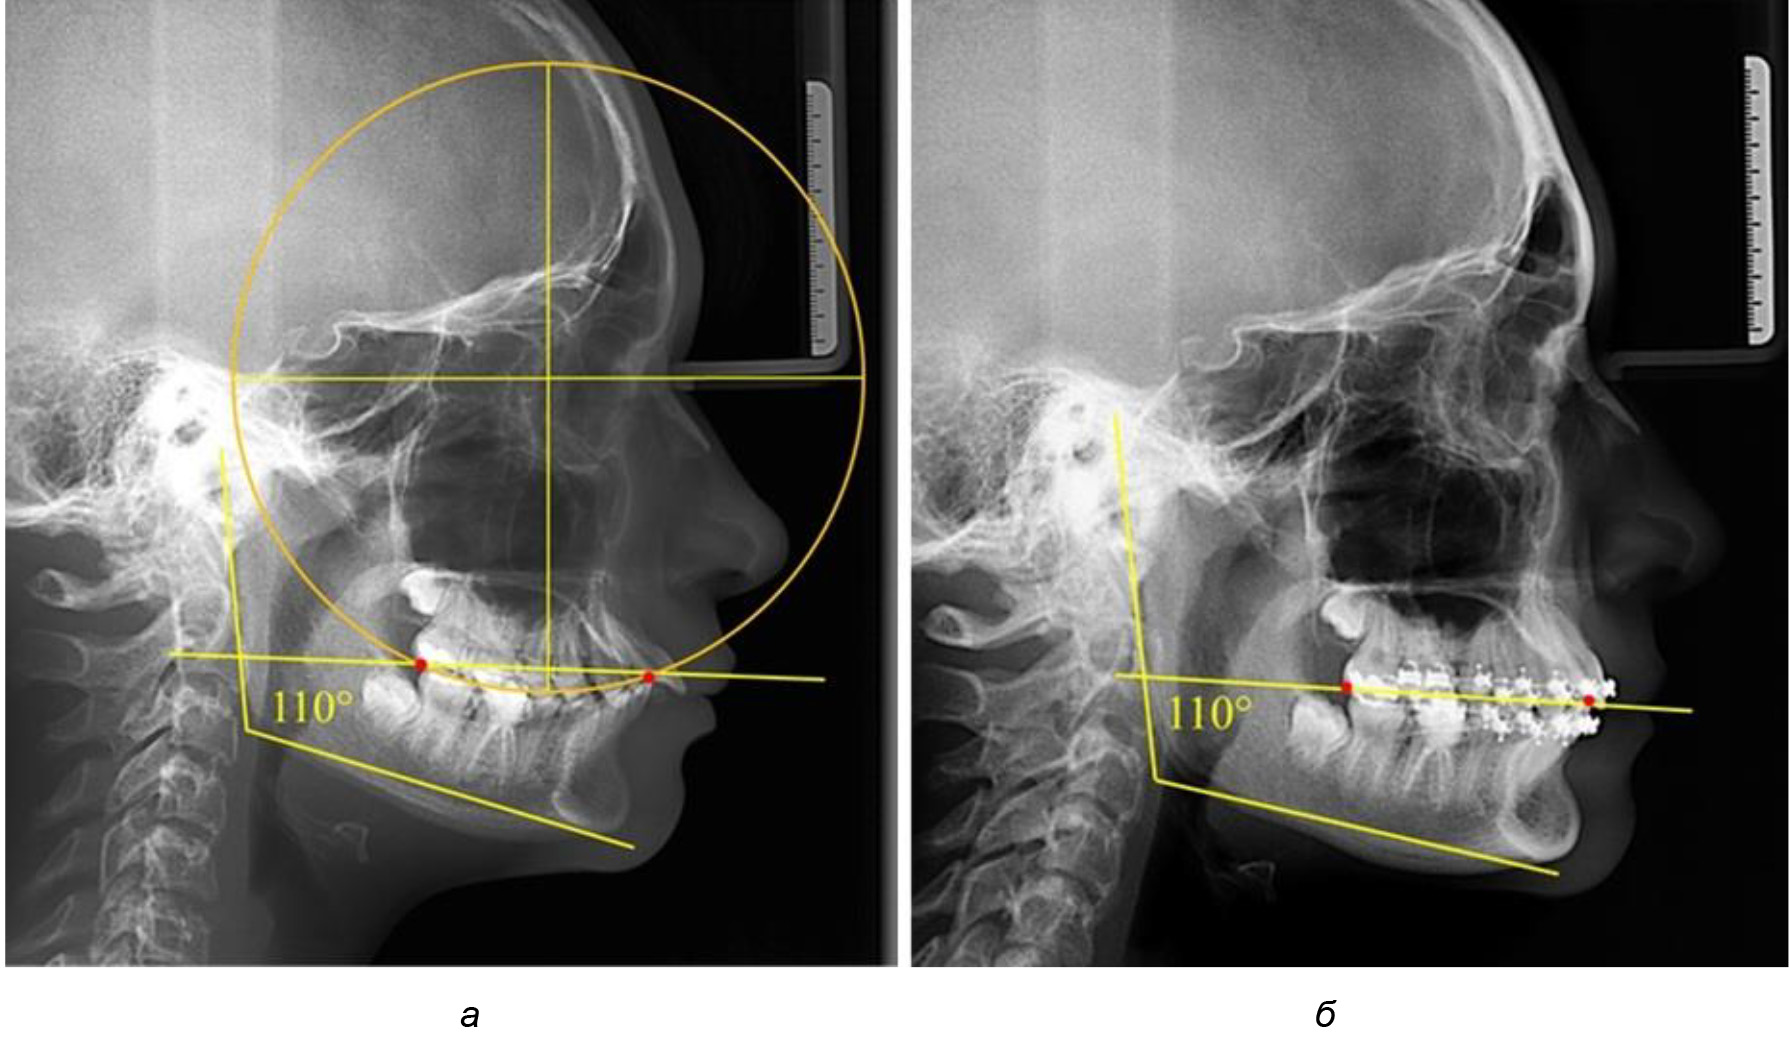

Рис. 2. Особенности кривой Spee на ТРГ (а) и ОПТГ (б) у людей с признаками вертикального роста

На рентгенограммах людей 2-й подгруппы (30 человек с нейтральным типом роста) величина угла нижней челюсти в среднем составила (120,34 ± 2,19) ° и характеризовала нейтральный тип нижней челюсти.

Глубина кривой Spee в среднем по 2-й подгруппе составил (3,54 ± 0,58) мм, что было незначительно меньше, чем при анализе аналогичного показателя 1-й подгруппы.

Достоверных различий с показателями, полученными при анализе ТРГ и ОПТГ, нами не отмечено (р ˃ 0,05). Деление величины радиуса круга к длине окклюзионной линии составило 1,612 ± 0,02, что, так же как и в 1-й подгруппе, было близким по значению к числу Фибоначчи (1, 618).